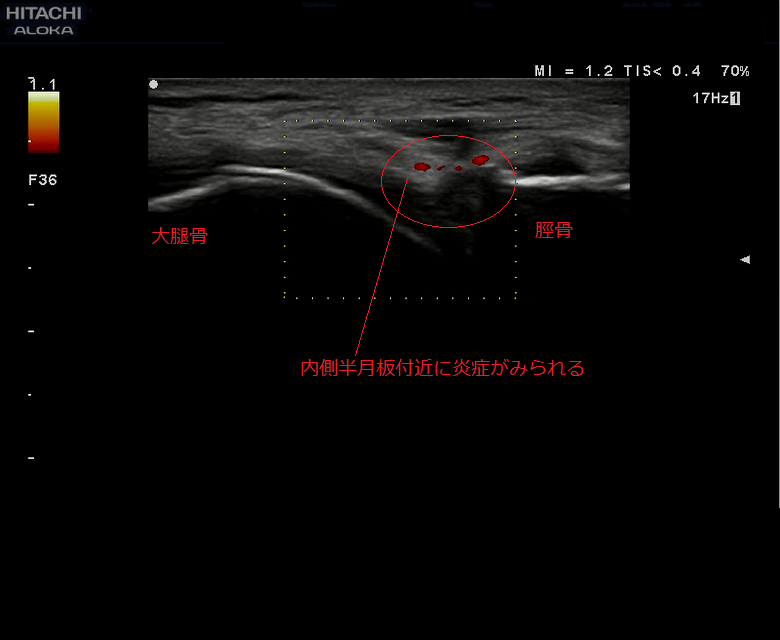

楽天市場】【内側半月板】《固定用》膝サポーター|エクスエイド。楽天市場】【内側半月板】《固定用》膝サポーター|エクスエイド。膝サポーター 膝 サポーター 医療用 医療 スポーツ 内側半月板。米10キロ 天のつぶ 雪若丸(各5キロ×1袋)。内側半月板損傷|おすすめの膝サポーター。半月板損傷 |SPORTS MEDICINE LIBRARY|ザムスト(ZAMST)。内側半月板損傷におすすめの膝サポーター集 コルセットミュージアム。半月板損傷 |SPORTS MEDICINE LIBRARY|ザムスト(ZAMST)。半月板損傷(断裂)meniscus-injury(rupture)について | ゆうき。右膝内側半月板損傷 前野整形外科 - 【公式】esaote 日本で唯一。外側半月板損傷|おすすめの膝サポーター。エクスエイドニー 固定用内側半月板損傷用 右膝用です。半月板損傷 – McDavid|サポータ-ブランドのマクダビッド。※外側半月板損傷 左膝膝としても使えます定価16980円でした。1度着用いたしました。円板状半月板損傷を治す!>膝サポーターのメソッド。固定力がとてもあり、安定してます。サイズM